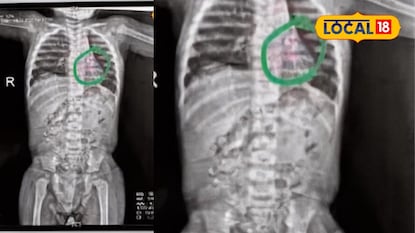

छत्रपती संभाजीनगर : पैठण गेट परिसरात खेळत असताना सुमारे 15 महिन्यांच्या एका चिमुकल्याने नकळत खडा गिळल्याची गंभीर घटना घडली. गिळलेला खडा श्वासनलिकेत अडकून पुढे फुप्फुसाच्या डाव्या बाजूला पोहोचल्याने बालकाला श्वास घेण्यास तीव्र अडचण निर्माण झाली. परिस्थिती गंभीर होताच कुटुंबीयांनी तत्काळ त्याला शासकीय वैद्यकीय महाविद्यालय व रुग्णालय (घाटी) येथे दाखल केले.

तपासणीनंतर कान-नाक-घसा विभागाचे प्रमुख डॉ. सुनील देशमुख यांच्या मार्गदर्शनाखाली वैद्यकीय पथकाने तातडीने ‘ब्रॉन्कोस्कोपी’ प्रक्रिया करण्याचा निर्णय घेतला. भूल देऊन दुर्बिणीच्या सहाय्याने श्वासनलिकेत ‘फोरसेप’ (चिमटा) टाकत अडकलेला खडा अत्यंत कौशल्याने बाहेर काढण्यात आला. ही प्रक्रिया यशस्वी ठरल्यानंतर बालकाची ऑक्सिजन पातळी स्थिर झाली असून प्रकृतीत सुधारणा झाली आहे.